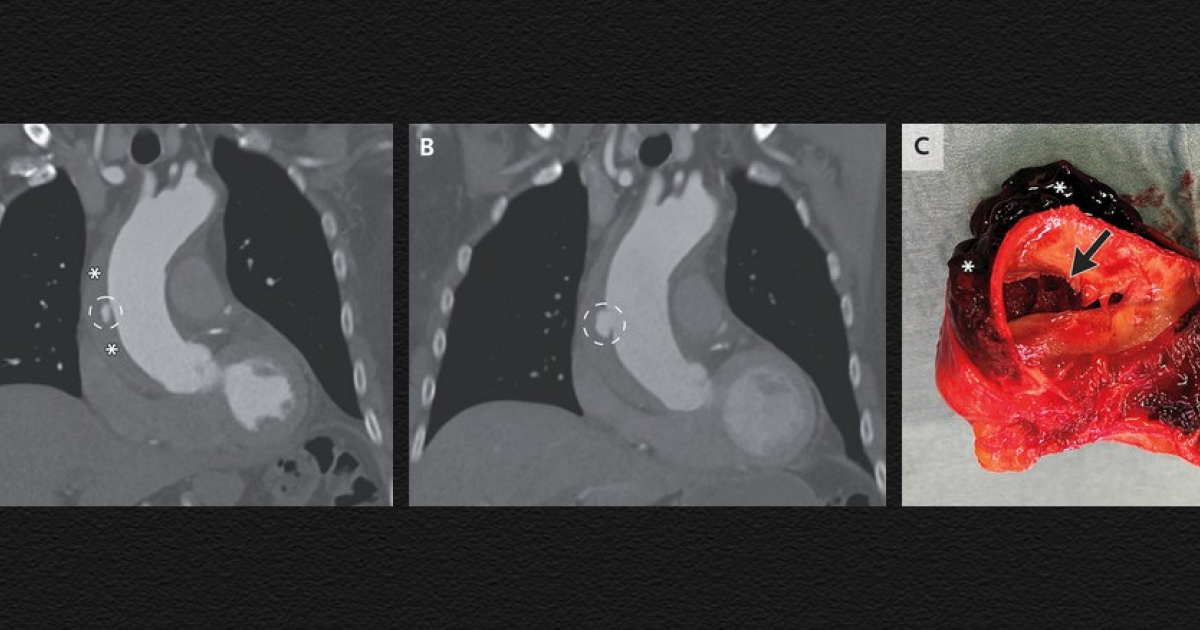

Нидерландцу удалили гематому в стенке аорты.

Нидерландцу удалили гематому в стенке аорты. Нидерландцу удалили гематому в стенке аорты